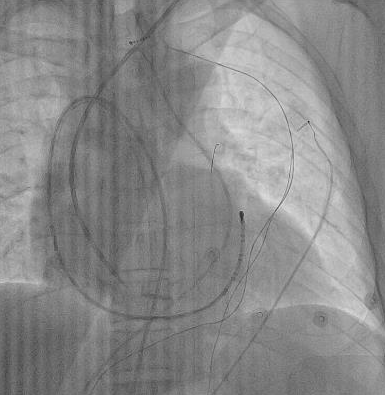

▲冠脉介入球囊扩张技术成功突破房间隔。

但困难接踵而来,外鞘反复尝试不能跨过房间隔,随后团队采用PBMV专用螺旋钢丝支撑和扩张鞘仍未成功通过房间隔。最终,团队另辟蹊径,采用冠脉介入球囊扩张技术成功突破。这一过程中,腔内超声、三维标测系统和冠脉介入技术的融合,为复杂解剖结构下的操作提供了坚实的支撑。

▲刘星采用“倒勾”导管操作方法进行肺静脉隔离。

经过数小时的精细攻坚,团队在突破多重解剖限制后,针对心脏反位、导管操作空间受限的核心难题,采用“倒勾”式消融导管操作技术,有条不紊地完成了双侧肺静脉电隔离。术后,患者恢复正常窦性心律,无并发症发生,目前已顺利康复出院,回归正常生活。